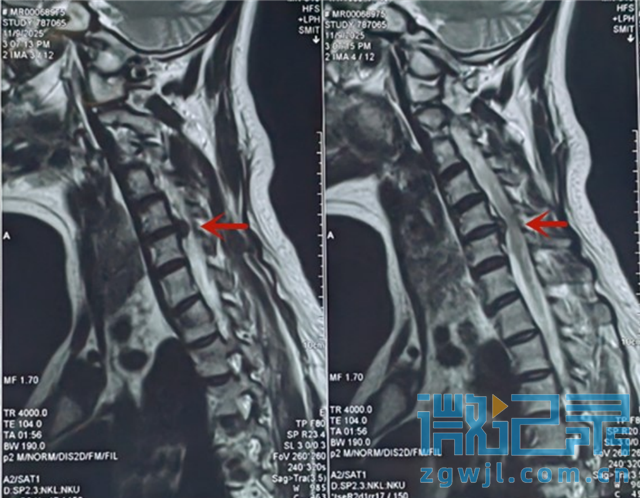

患者颈5/6椎间盘突出